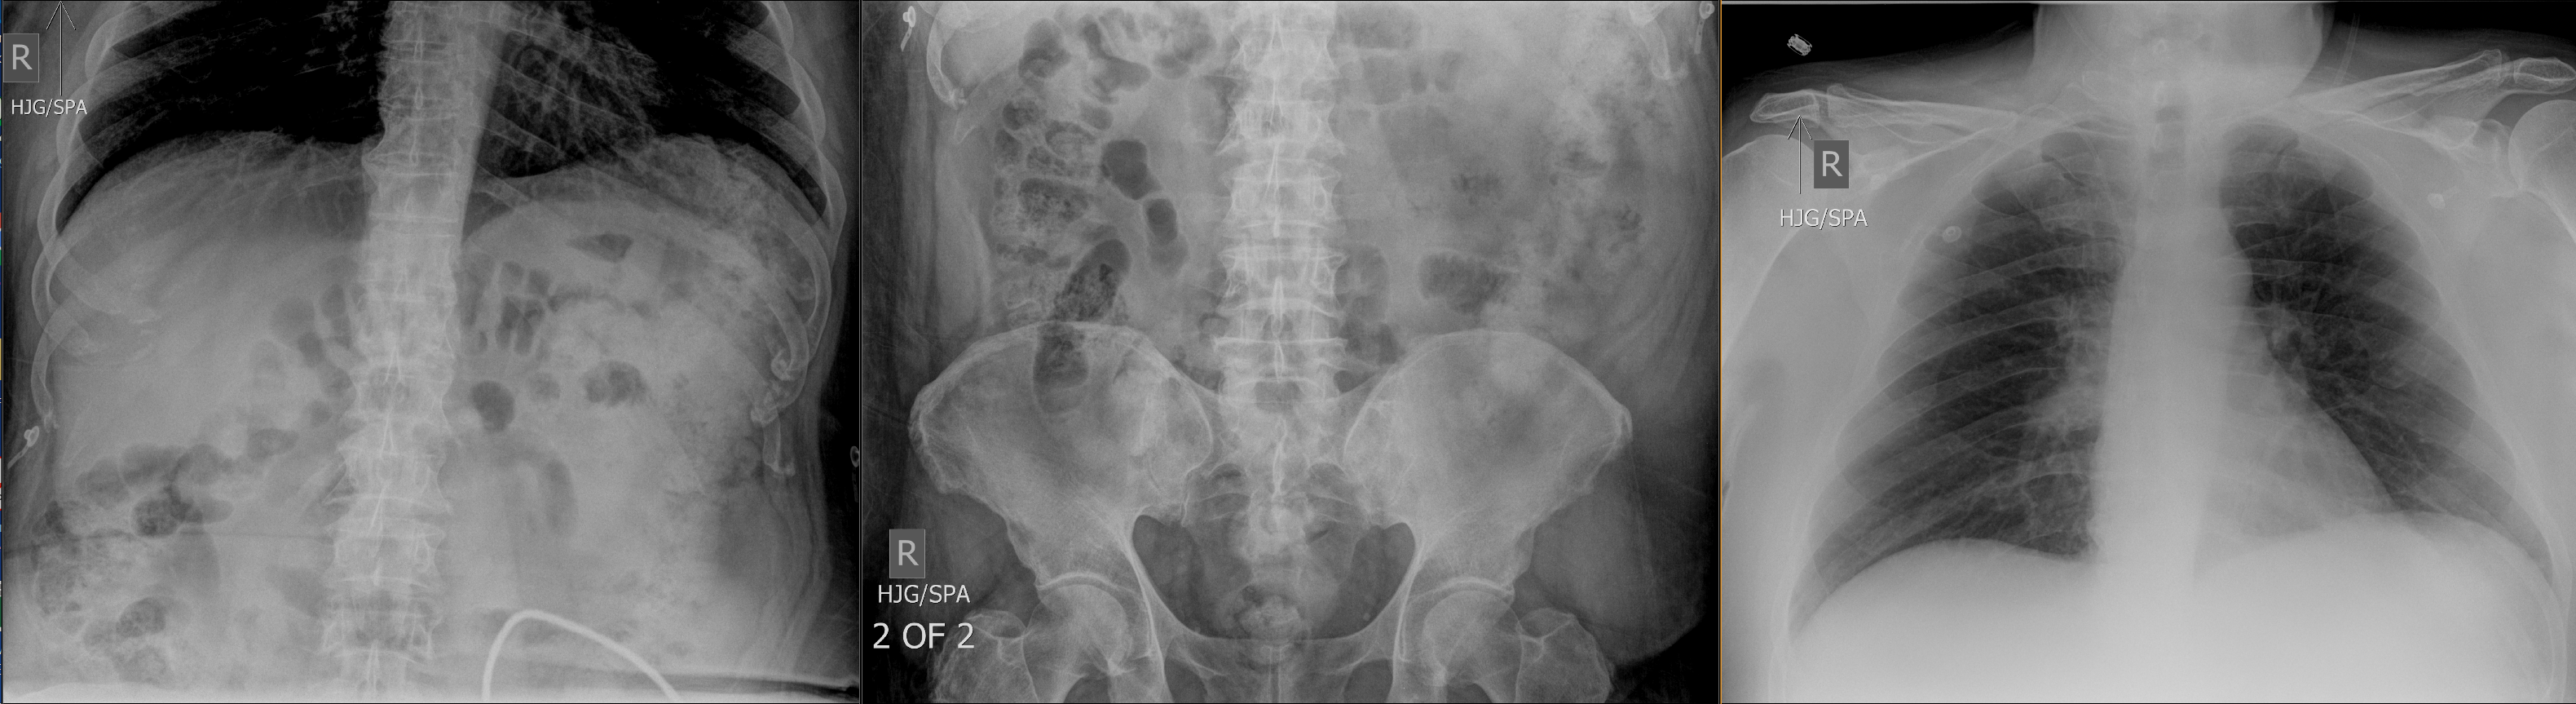

The patient likely does not have cholecystitis. An acute abdominal series may reveal free air in the abdomen, dilated bowel, pneumatosis, portal venous gas, or be normal. A CT scan is a reasonable first step if clinical suspicion of pathology is high. For this patient, the abdominal series was initially obtained in the ED.

Pertinent Imaging Observations

Click on the links below to view images from the study, and assess these key findings as best you can.

View the full study if you'd like to take a look yourself.